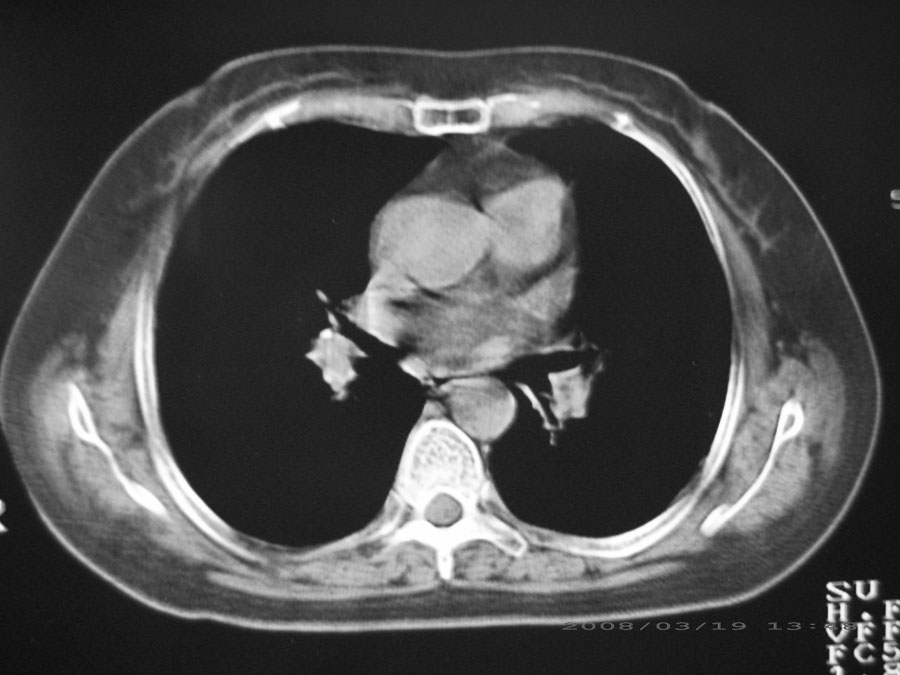

本病例主要是癌性淋巴管炎与结节病的鉴别。好好查查吧。

双肺网状结构,小叶间质结节状增厚,考虑结节病

综合大家意见,结核、结节病、肺泡细胞癌均有可能,间质性肺炎暂不考虑,病灶纠集不明显,纵隔未见钙化淋巴结,尘肺可能性不大,但还是要密切结合临床诊断。

今天重新仔细看了看,矽肺确实不能除外,病灶主要表现为间质结节及纤维化。好好问问病史吧。